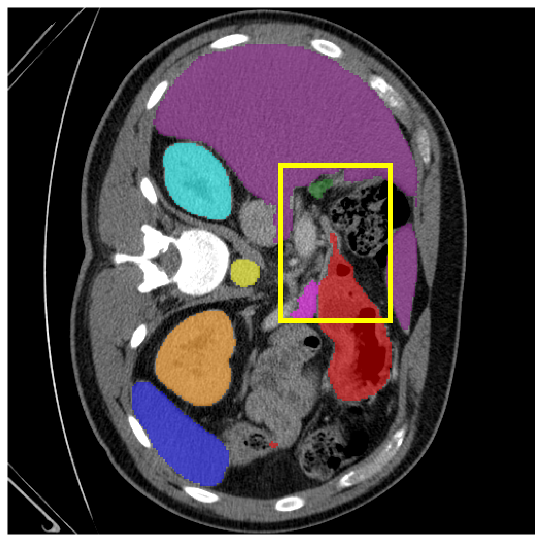

4.3.2 Visual Comparisons

Visualization of our method on the Synapse and ACDC datasets is shown in Fig. 3(a) and Fig. 3(b). For the Synapse dataset illustrated in Fig. 3(a), FCT failed to accurately segment SM and GB, while MERIT achieved precise segmentation of SM but struggled with GB. In contrast, our method achieved accurate segmentation of both SM and GB. Regarding the ACDC dataset shown in Fig. 3(b), while previous methods achieve comparable segmentation of the Myo and LV to the GT, they exhibit noticeable errors on the RV, including invasion into adjacent organs and misrecognition. On the other hand, our method accurately segments across all three structures Myo, LV, and RV, performing as precisely as the GT. We demonstrate the superiority of our method quantitatively and qualitatively.